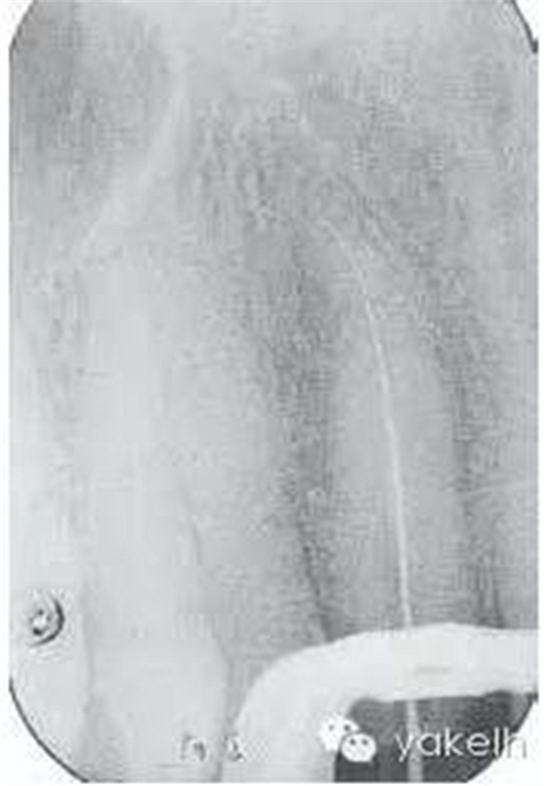

¤¤局麻下,制備上頜切牙印模;拆除12烤瓷全冠;評估患牙的可修復(fù)性;橡皮障隔離患牙,定位根管口,使用GG鉆和不銹鋼手用銼去除根管內(nèi)的牙膠;全程使用大量次氯酸鈉沖洗根管;根尖定位儀測量根管工作長度,拍攝X線片確定(圖6.3.3);使用不銹鋼手用銼和鎳鈦旋轉(zhuǎn)器械進(jìn)行根管預(yù)備,EDTA沖洗根管,再用次氯酸鈉進(jìn)行終末沖洗;紙尖干燥根管;使用牙膠輔以根管封閉劑、采用熱垂直加壓技術(shù)充填根管的根尖5mm;建議樁核冠修復(fù)。

圖6.3.3 確定工作長度的X線片顯示,12根管通暢至全長;特征是根管的根尖1/3向遠(yuǎn)中腭側(cè)彎曲。